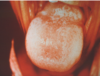

What is this radiographic & clinical findings?

Periapical cyst

shows inflammation at site

abscess developed fistula tract thru

soft tissue. Pt will have pain until

pressure is released